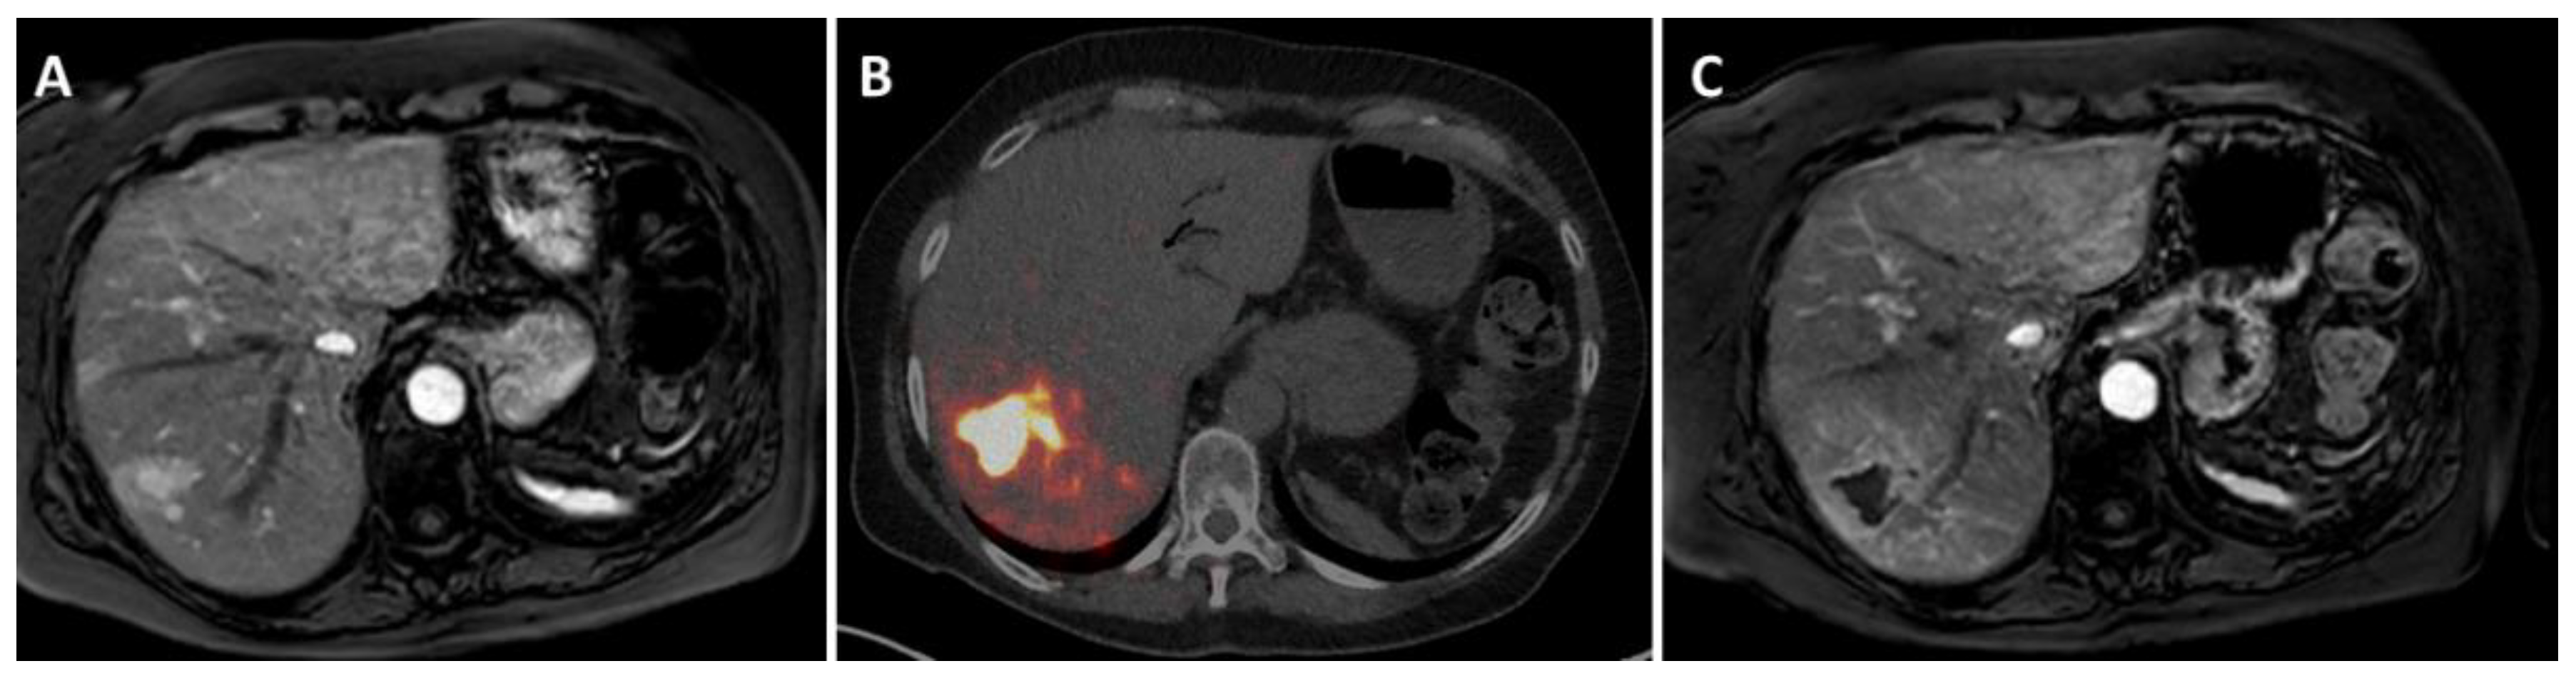

2. How Is Radioembolization Performed?

- Braat, A.J.A.T.; Bruijnen, R.C.G.; van Rooij, R.; Braat, M.N.G.J.A.; Wessels, F.J.; van Leeuwaarde, R.S.; van Treijen, M.J.C.; de Herder, W.W.; Hofland, J.; Tesselaar, M.E.T.; et al. Additional holmium-166 radioembolisation after lutetium-177-dotatate in patients with neuroendocrine tumour liver metastases (hepar plus): A single-centre, single-arm, open-label, phase 2 study. Lancet Oncol. 2020, 21, 561–570. [Google Scholar] [CrossRef]